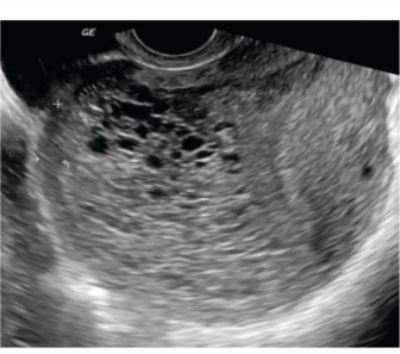

What is the diagnosis based on the ultrasound findings of an early pregnancy?

Explanation: ***Complete mole*** - Shows the classic **"snowstorm"** or **"Swiss cheese"** appearance on ultrasound due to multiple **cystic spaces** representing hydropic villi. - **No fetal parts** or **fetal heart activity** are visualized, and **beta-hCG levels** are markedly elevated (>100,000 mIU/mL). *Partial mole* - Ultrasound shows **mixed echogenic pattern** with **focal cystic changes** and **fetal parts** may be present. - Associated with **triploid karyotype** (69,XXX or 69,XXY) and **lower beta-hCG levels** compared to complete mole. *Invasive mole* - **Cannot be diagnosed** by ultrasound alone as it appears similar to complete mole initially. - Diagnosis requires **histopathological evidence** of **myometrial invasion** and **persistently elevated beta-hCG** after evacuation. *Choriocarcinoma* - Ultrasound shows **heterogeneous mass** with **areas of hemorrhage** and **necrosis**, not the classic snowstorm pattern. - Develops after **any type of pregnancy** and shows **rapid metastatic spread** with **very high beta-hCG levels**.